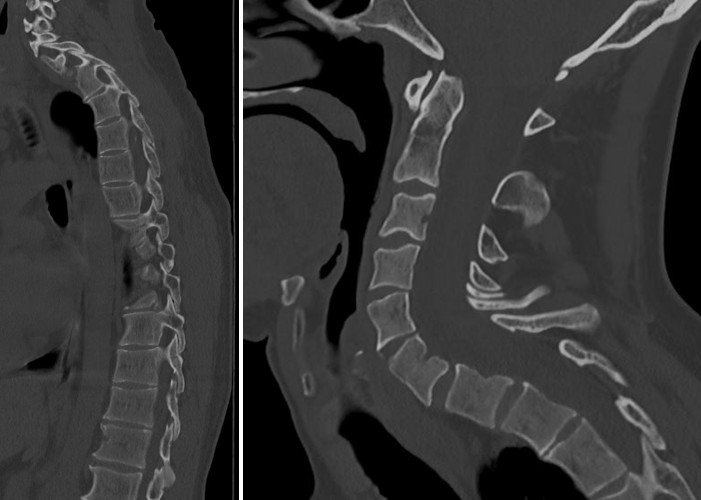

My backbone (spinal column)

Here are some X-rays of my spinal column and my cervical vertebrae in profile view.